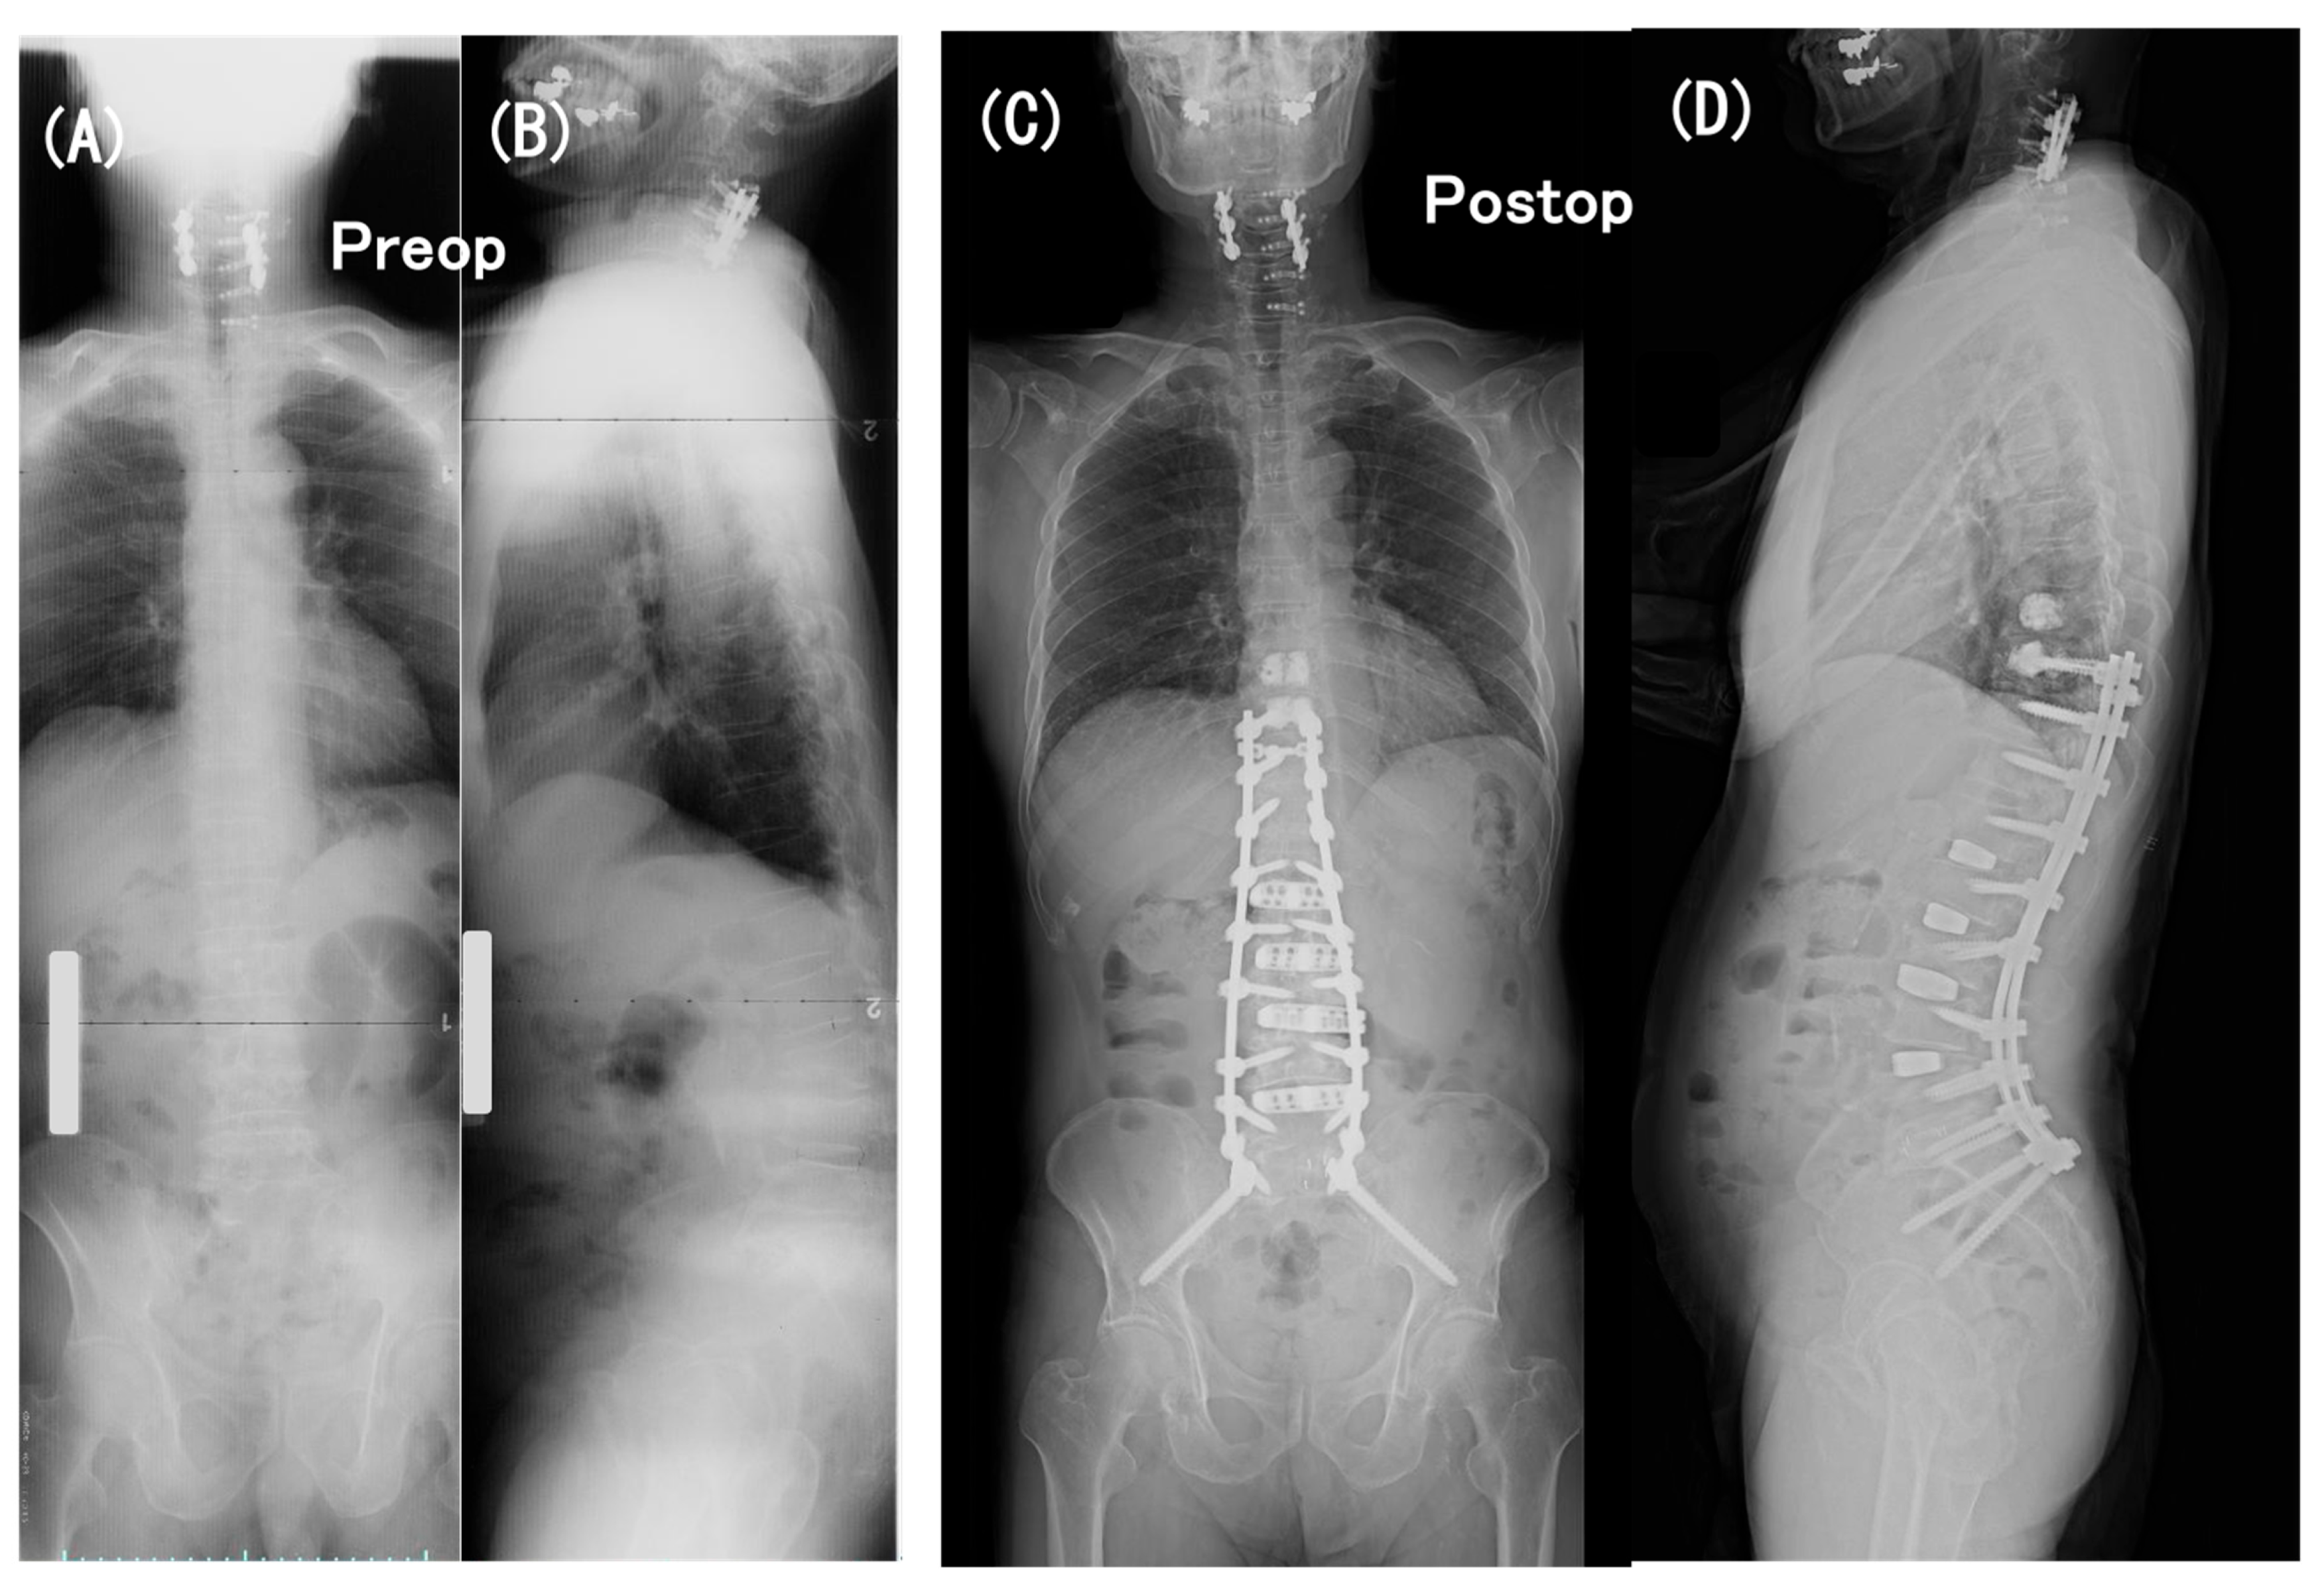

3.6. Case Presentation

- Case no. 6

- 2.

- Case no. 4